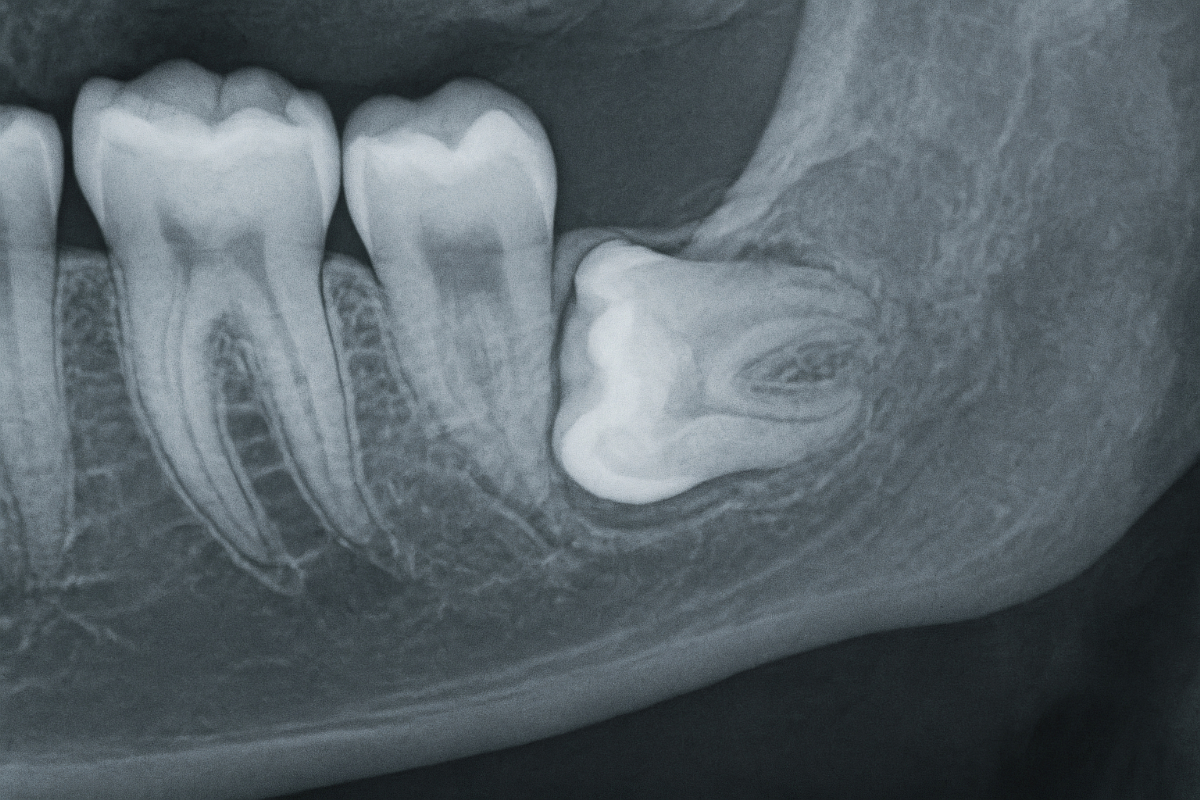

最初に行われるのが、口の中の状態確認と画像検査です。

視診に加えてレントゲン撮影を行い、親知らずの向きや埋まり方、隣の歯との位置関係を把握します。特に下顎の親知らずでは、神経との距離を確認することが重要です。必要に応じてCT撮影が行われ、より立体的に状態を把握します。

これらの情報をもとに、抜歯の難易度や処置方法、注意点について説明が行われます。